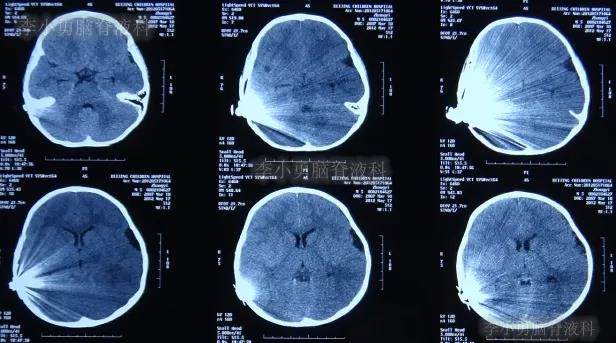

入院当天脑CT检查发现,脑积水又有加重表现(图-8)。

图-8:2012年6月7日脑CT脑积水加重

入院治疗18天即2012年6月25日,查脑CT示脑室有缩小(图-10)。

图-10:2012年6月25日脑CT